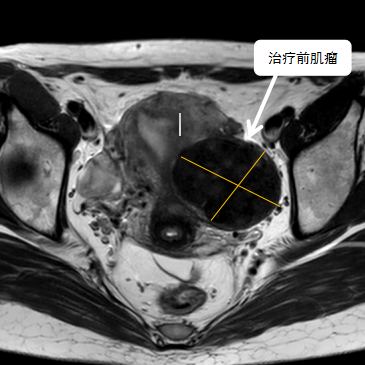

38歲的袁女士多年前發(fā)現(xiàn)子宮肌瘤,病情雖不嚴(yán)重,但是最近三年腫瘤在逐步增大,最大的肌瘤將近6公分,袁女士下一步面臨生育問題,如果不處理子宮肌瘤,懷孕期間激素水平的變化有可能會(huì)導(dǎo)致肌瘤快速增大;如果常規(guī)手術(shù)處理肌瘤,由于瘢痕粘……